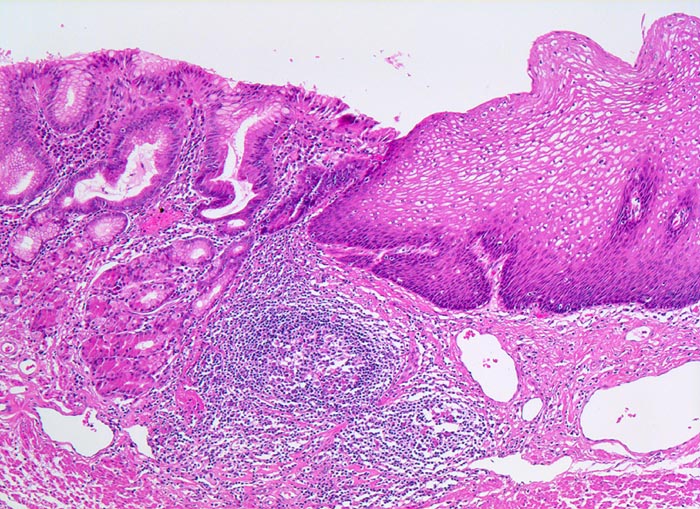

Ausschnitt aus dem gastroösophagealen Übergang. Rechts im Bild die akanthotisch verbreiterte Ösophagusschleimhaut mit einer Verbreiterung der Basalzellschicht (dunkle Zellen) als Zeichen für Reflux. Daran angrenzend Magenschleimhaut (mit Schleimdrüsen und spezialisierten Magendrüsen) mit geringgradigem Entzündungsinfiltrat im Stroma. Keine intestinale Metaplasie. Lymphfollikel in der Submukosa.

Morphologische Veränderungen bei Reflux: Hyperplasie der Basalzellschicht (Basalzellschicht normalerweise 10-15% der Schleimhautdicke), Hyperämie und Verlängerung der bindegewebigen Papillen auf >50% der Schleimhautdicke, Granulozyten in der Mukosa (vor allem eosinophile). Die Zylinderepithelmetaplasie und die Barrettmukosa sind ebenfalls eine Folge von vermehrtem Reflux.